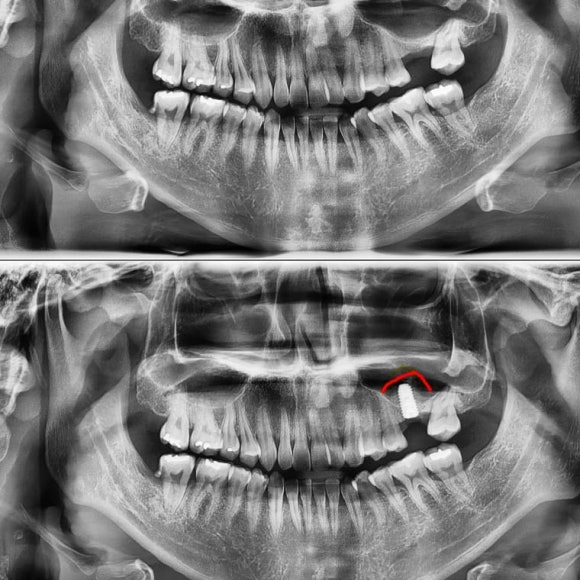

60대 남성의 임플란트, 상악동 수술, 뼈이식을 한 사례입니다.

임플란트 상악동 뼈이식

사진에서 보듯 발치 한 부위를 비워둔지가 오래 되어서

해당부위 뼈의 양이 부족하고, 반대편 치아가 정출 되었으며, 뒤 치아가 쓰러져 있음을 알 수 있습니다.

임플란트 수술과 상악동 수술 그리고 뼈이식을 진행하고

<6개월 뒤>

뼈이식재가 뼈가 잘 되었는지 여부

임플란트가 뼈와 잘 고정되었는지

를 확인합니다.

상악동 수술과 뼈이식을 동반한 임플란트 수술을 5분만에 끝낼 수 있었습니다.

리더스진 치과 상악동 수술

상악동 수술과 뼈 이식은 치과의사들이 매우 부담스러워 하는 치료 입니다.

리더스진 치과에서는 특별한 기술과 장비를 사용하여

성공율이 99%에 가까울 뿐 아니라

대학 병원에서 45분 이상이 걸리는 수술을

5분 이내로 마무리 합니다.